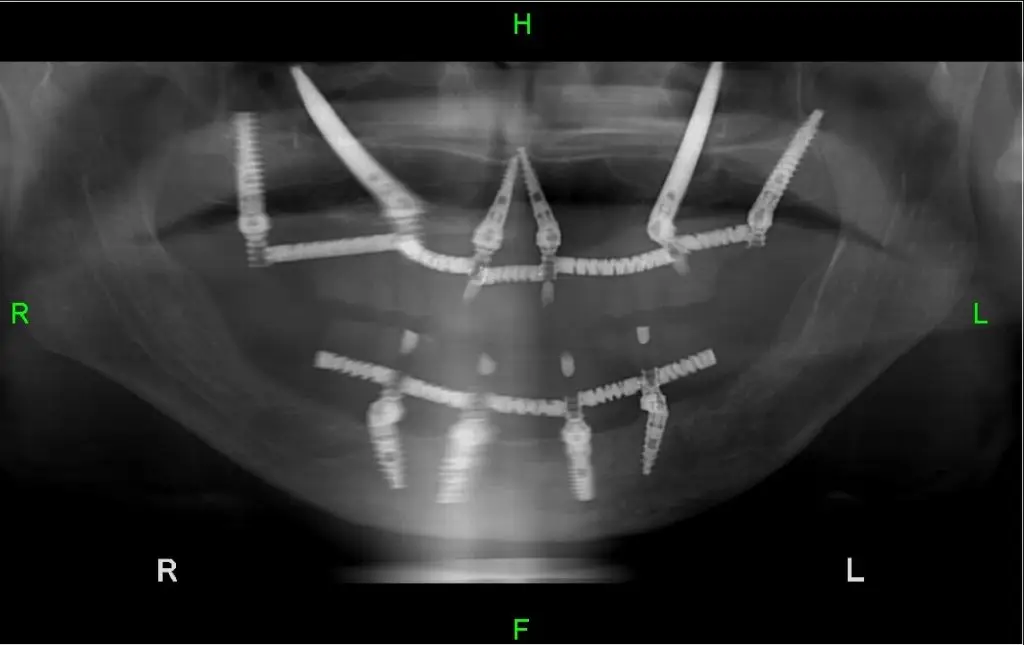

In order to perform the dental implant into the Zygoma, dentists uses Zygomatic implants, dental implants that are longer that reach higher than the jawbone area, and can reach and be screwed into the Zygoma bone.

This way we can bypass the problem of bone deficiency in the upper jawbone and succeed performing the same-day dental implant even in complicated cases of bone deficiency, and the treatment is fit perfectly to the patient.